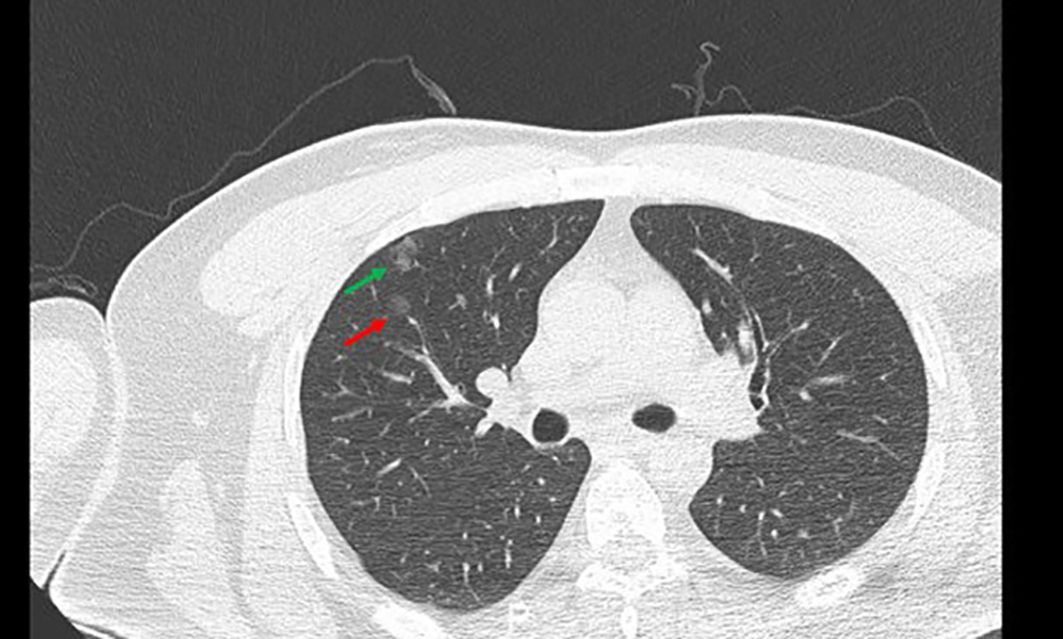

The specific operation involved exercising the patient’s respiratory condition before the operation. Before puncture, a Philips CT scan was obtained with the assistance of a fence to determine the puncture point and mark it. Disinfect the puncture point and its surroundings with 75% alcohol with the puncture point as the center, followed by wiping it clean with disinfectant paper towels remaining alcohol for the puncture operation. A 2-mL syringe was used to extract 2% lidocaine, and the pleura was anesthetized layer by layer at the puncture location. The syringe needle was left on the patient, and the CT was rescanned. The scanning range was 3 cm up and down with the puncture layer at the center, and the layer thickness was 2 mm to reduce the radiation on the patient while scanning the nodules as much as possible. The position between the syringe needle and the nodule was observed after scanning. The angle was adjusted, and the depth was calculated. At the same time, the location of the formation was marked after the injection of medical glue, usually 5 mm outside the lung field of the lesion. With an 18-G Chiba puncture needle (GALLINI S.R.L.), the needle was inserted in the direction of the original 2-mL syringe needle. The CT scanner was rescanned to determine the arrival of the expected marking point, the core of the Chiba puncture needle was pulled out, and the medical glue (Beijing Compont Medical Devices Co., Ltd.) was injected. The injection speed was 0.15–0.2 mL with a 1-mL syringe, and 0.1 mL of 5% glucose solution was injected to ensure that the residual medical glue inside the Chiba needle was fully injected into the lungs. The needle was left in place for 3–5 s, after which the needle was quickly removed. The puncture point was wrapped with a dressing. Chest CT (Figure 3) revealed the position of the medical glue in relation to the nodule and whether there was any complication in the lung. After confirming the patient’s condition, the patient was sent to the operating room for VATS surgical treatment.

Figure 3

Preoperative positioning with medical glue. the red →, the location of GGN; the green →, medical glue; GGN, ground glass nodules.